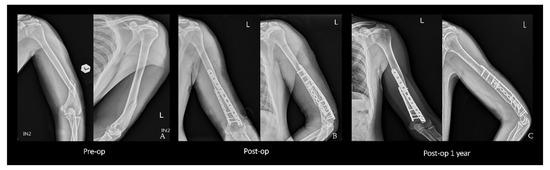

2.2. Surgical Technique

2.4. Single Plating

2.5. Postoperative Protocol